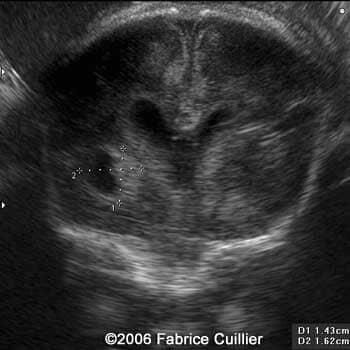

An additional endovaginal scan was performed. There were one large cyst on the right hemisphere and multiple peripheral cysts. The corpus callosum artery was identified. Fetal biometry was in concordance with the gestational age. Karyotyping was offered (46XX). A PCR was performed in the amniotic fluid sample. The result was positive for the Toxoplasma gondii DNA.

Right parasagittal scan at 30 weeks showing ventriculomegaly, echogenic areas and anterior parasagittal marked hyperechogenecity zone

4

5